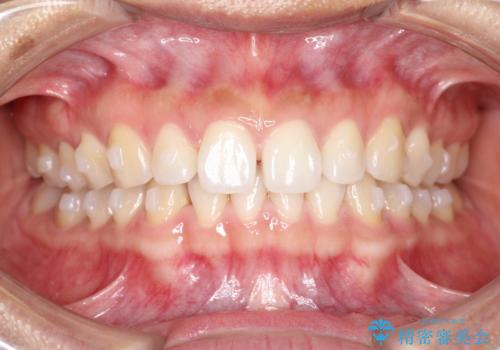

すきっ歯のインビザラインによる目立たない矯正

- すきっ歯を治したいとのことで来院されました。

上下ともに前歯に隙間がありました。

目立たない装置をご希望のためインビザラインで矯正治療を行うこととしました。

使用時間を守っていただけたので、スムーズに治療を終わることができました。